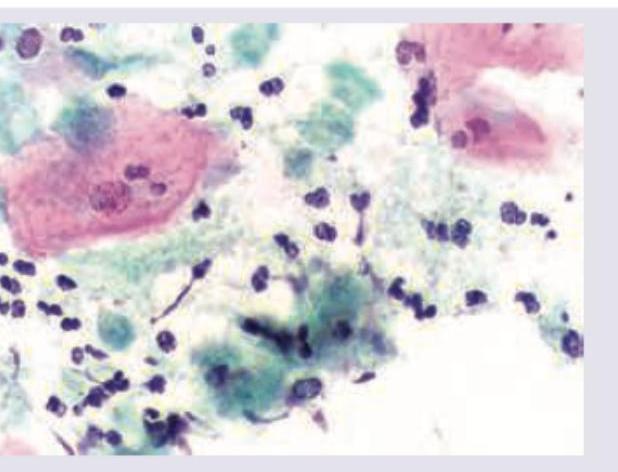

Question 1: A wet mount preparation of vaginal discharge shows the following. Identify the organism responsible.

- A. Trichomonas vaginalis (Correct Answer)

Explanation: ***Trichomonas vaginalis*** - The image shows numerous flagellated protozoa, characterized by their **pear-shaped appearance** with **jerky motility** on wet mount examination. - **Trichomonas vaginalis** is a flagellated protozoan parasite causing vaginitis, typically presenting with frothy, yellow-green vaginal discharge and strawberry cervix. - Wet mount microscopy showing motile trophozoites is the classic diagnostic method for trichomoniasis. *Neisseria gonorrhoeae* - This bacterium is a **gram-negative diplococcus**, typically seen intracellularly within neutrophils on Gram stain. - It does not present as flagellated protozoa on microscopy. *Chlamydia* - **Chlamydia trachomatis** is an obligate intracellular bacterium, not visible on routine wet mount microscopy. - Diagnosis requires specialized staining (Giemsa), immunofluorescence, or molecular tests (NAAT). *Treponema pallidum* - This is a **spirochete** responsible for syphilis, typically identified using dark-field microscopy from ulcer exudate or serological tests. - It does not present as the large, flagellated protozoa characteristic of Trichomonas.